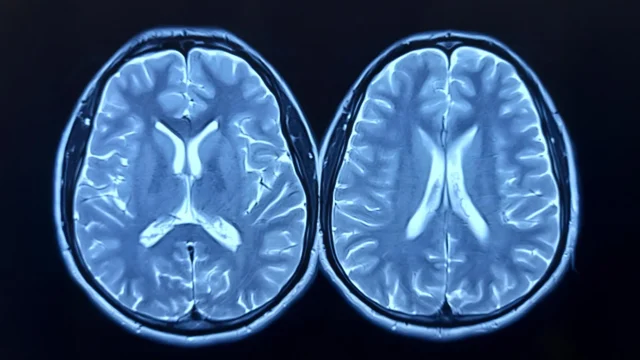

用 MRI 測量大腦年齡

發表於 運動科學與健康雜誌這項研究探討了定期有氧運動是否可以減緩或逆轉科學家所說的“大腦衰老”。大腦年齡是使用磁共振成像 (MRI) 估算的,反映了大腦年齡與人的實際年齡的比較。大腦預測年齡差異(brain-PAD)越高意味著大腦看起來更老。之前的研究已將這一指標與較弱的身體和認知表現聯繫起來。並且死亡風險較高

研究人員使用 MRI 掃描測量大腦結構,並通過研究開始時和 12 個月後的峰值攝氧量 (VO2peak) 評估心血管健康狀況。